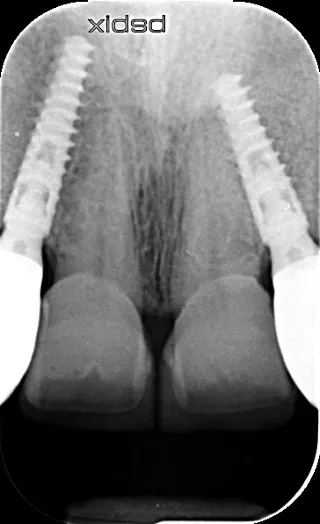

17a-b-c-d. Retro-alveolar X-rays at the end of treatment. Note bone behavior around the 4 implant collars. Soft tissue height above each collar was 3 to 4 mm.